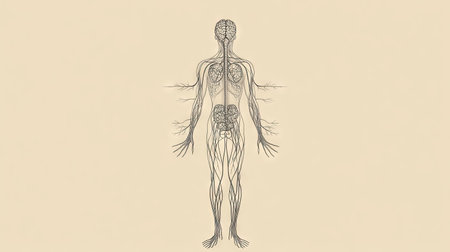

Human nervous system diagram, centrally aligned with plenty of blank space around for copy. -

A detailed anatomical diagram of the human nervous system, highlighting the brain, spinal cord, and peripheral nerves, arranged for educational clarity